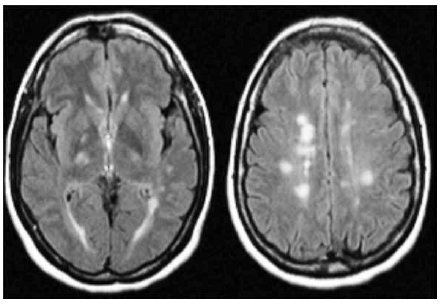

Paciente do sexo feminino, 25 anos, com queixa de fraqueza e dormência à esquerda há 3 dias. Tem antecedente de neurite óptica à esquerda há dois anos. Ao exame, apresenta hemiparesia com sinais de liberação piramidal à esquerda, bem como hipoestesia nesse dimídio. Realizou a ressonância magnética de crânio mostrada a seguir.

A celularidade e a bioquímica do líquor eram normais. Diante do exposto, o diagnóstico é de